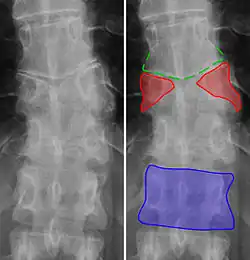

Butterfly vertebrae have a sagittal cleft through the body of the vertebrae and a funnel shape at the ends. This gives the appearance of a butterfly on an x-ray. It is caused by persistence of the notochord (which usually only remains as the center of the intervertebral disc) during vertebrae formation. There are usually no symptoms. There are also coronal clefts mainly in skeletal dysplasias such as chondrodysplasia punctata. In dogs, butterfly vertebrae occur most often in Bulldogs, Pugs, and Boston Terriers.[10]

-

Butterfly vertebra (red). Normal vertebra for comparison (blue). -

Volume rendering of a CT scan of the lumbar vertebral column, showing butterfly vertebrae at several levels, most typically in L1.